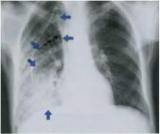

Рентгенологическое исследование легких — имеет решающее значение в диагностике пневмонии. Рентгенеграфия легких в 2 проекциях выявляет следующие характерные признаки:

а) уменьшение объема соответствующего отдела легких, тяжистость и деформацию легочного

рисунка мелко- и среднеячеистого типа; б) очаговые затемнения легких (они могут быть достаточно четкими при

выраженной карнификации альвеол);

в) перибронхиальную инфильтрацию в пораженном участке легочной тка-

ни;

г) проявления регионарного адгезивного плеврита (междолевые, парамедиастинальные спайки, облитерация реберно-диафрагмального синуса).